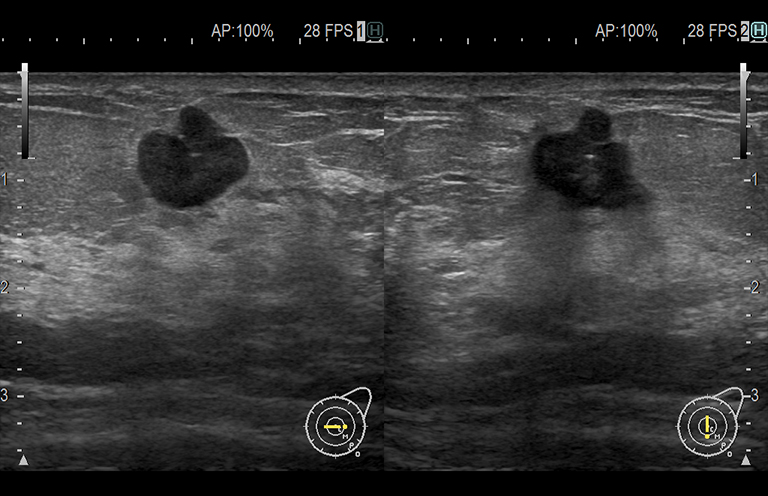

Aplicación: Mama

Función/análisis: Modo B(doble)

Comentarios: Mama